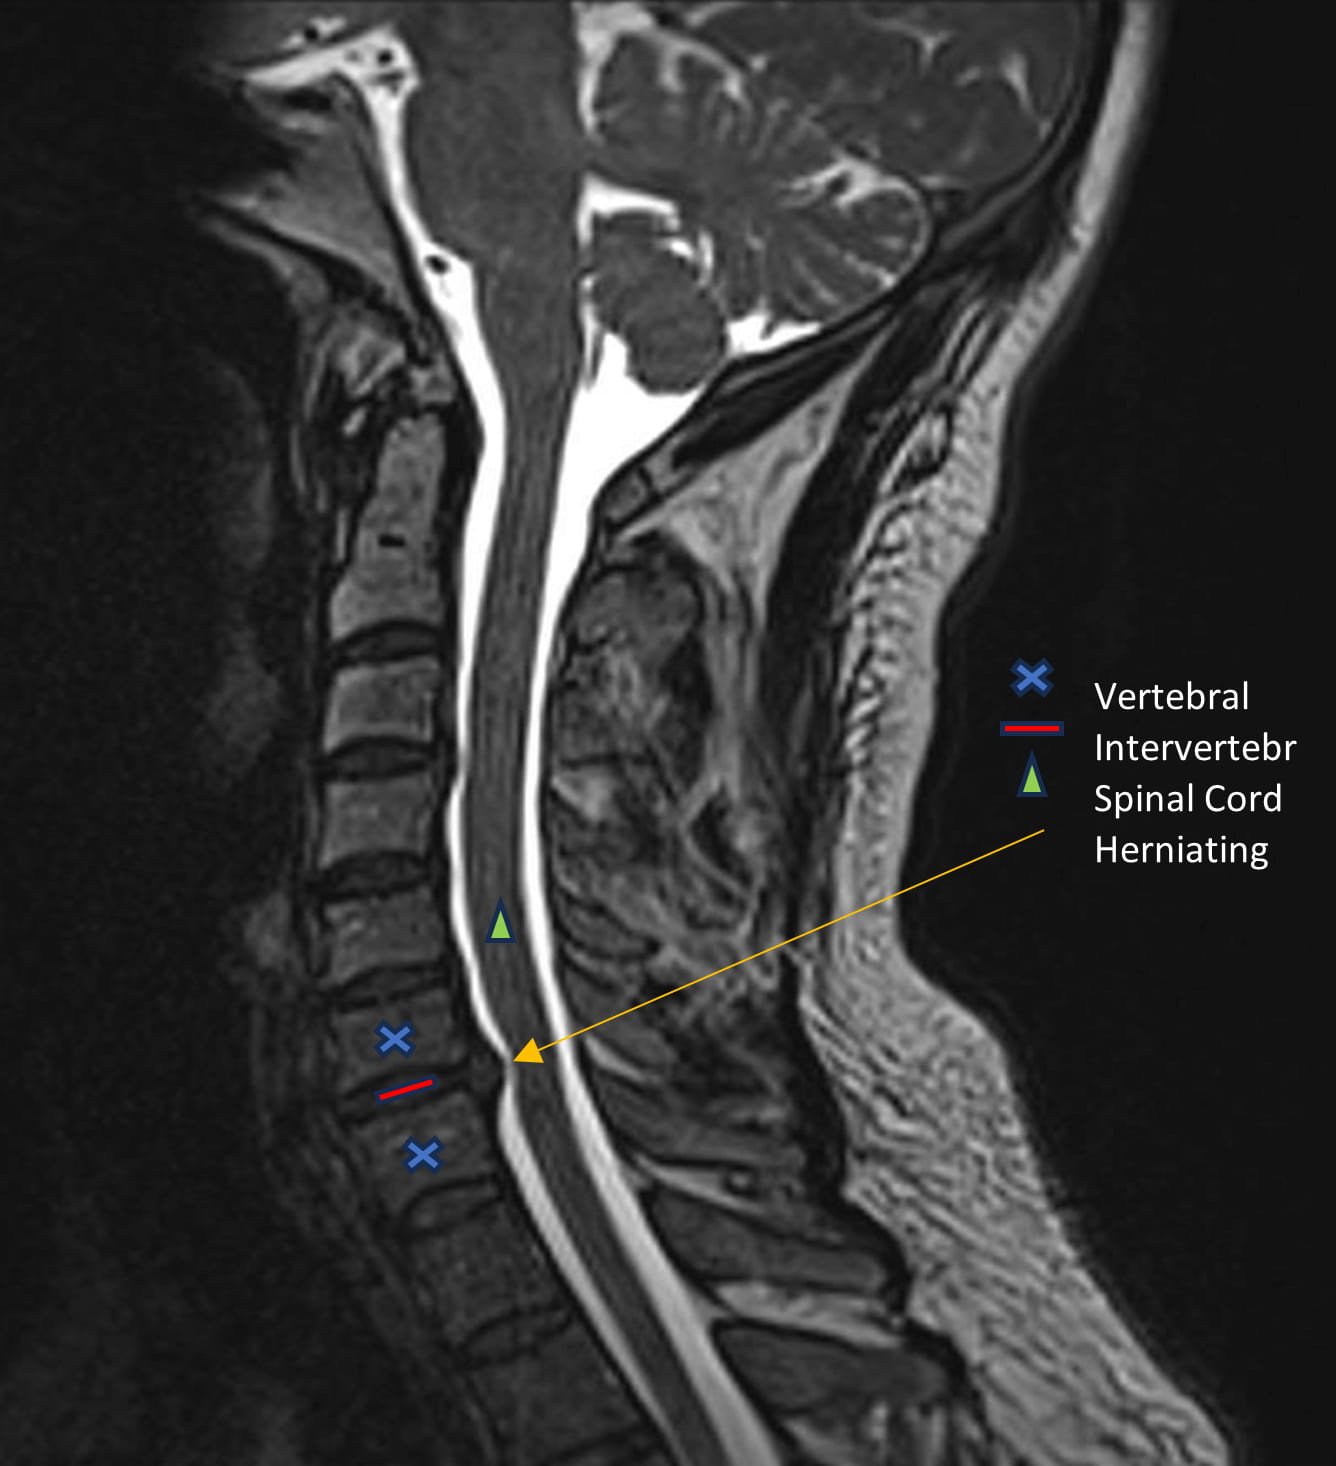

The term "pinched nerve" is a common way to describe cervical radiculopathy, and while it’s a good starting point, the actual condition is a bit more complex. Your cervical spine, the part of your spine located in your neck, is made up of vertebrae. Between these vertebrae are discs that act as cushions. Nerves exit the spinal cord through spaces in your cervical spine, called foramen, and travel to your shoulders, arms, and hands.

Cervical radiculopathy occurs when one of these nerve roots in your neck becomes compressed or irritated. This "compression" isn't necessarily a literal pinching sensation as much as it is pressure and inflammation on the delicate nerve tissue. This pressure can disrupt the nerve's normal function, leading to a variety of uncomfortable and sometimes painful symptoms.

- Herniated Discs: As we age, the discs between our vertebrae can dry out and become more prone to injury. A cervical herniated disc occurs when the soft, inner material of the disc protrudes or bulges out, potentially pressing on a nearby nerve root. This is a frequent cause of pinched nerve symptoms in the neck.

- MRI (Magnetic Resonance Imaging): MRI is often the gold standard for diagnosing cervical radiculopathy. It provides detailed images of soft tissues, including discs, ligaments, and nerve roots, allowing for clear visualization of herniated discs, nerve compression, and spinal stenosis. Sobel Spine and Sports can help coordinate necessary imaging if needed to ensure accurate diagnosis.

Disc protrusion at C6/7